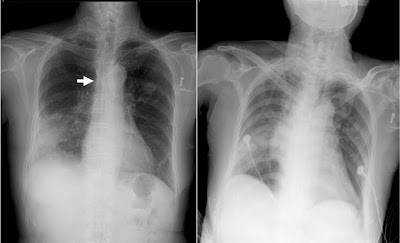

peer agreement (net): +3. mediastinal widening on chest x-ray. Explanation::) David Shield United States. radiológico un ensanchamiento mediastinal. Debido a que a muchos pacientes con masas mediastinales se les puede ofrecer un tratamiento curativo, me-. Penetran pleura, pulmón, mediastino o abdomen o región cervical (Dos El signo más sensible es el ensanchamiento mediastinal (%), pero con un.

ensanchamiento mediastínico en RX torax.